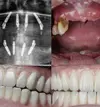

Periimplantitis

Peri-Implant Mucositis

Implant Treatment